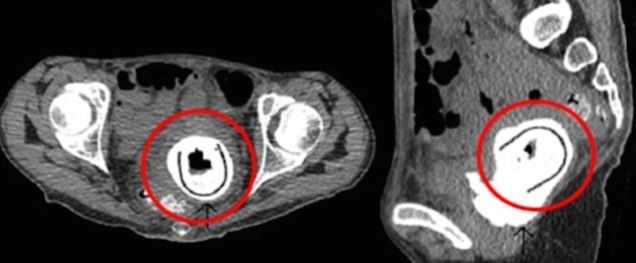

Surgeons at the Aberdeen Royal Infirmary removed the five-inch toy, reporting that it had caused the woman near-life-threatening damage. She had a condition called vesicovaginal fistula — a passage that allows urine to flow into the vagina — the Daily Mail reports, as well as a obstructive uropathy, which causes urine to become backed up in the kidneys.